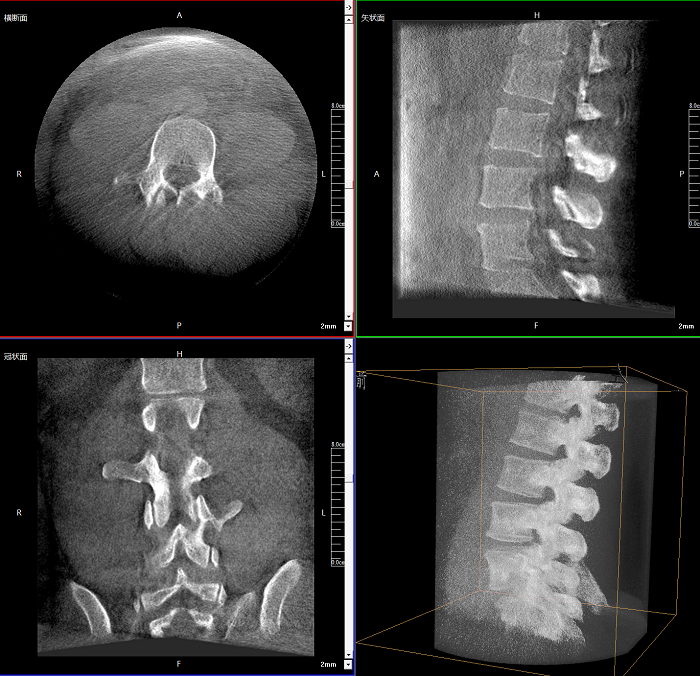

三維成像 全面觀(guān)察

任意視角、任意切面觀(guān)察

術(shù)中實(shí)時(shí)生成橫斷面、矢狀面、冠狀面及三維影像,可在任意切面、任意角度評估植入物和解剖結構的相對位置。

術(shù)中CT檢查 減少翻修概率

通過(guò)術(shù)中三維影像的檢查,可以立即發(fā)現植入物的錯位,減少不必要的第二次手術(shù),減少并發(fā)癥概率以及感染風(fēng)險。

較9英寸常規平板視野提升100%,幫助醫生迅速判斷椎體節段,定位手術(shù)部位。

400萬(wàn)像素成像

易于觀(guān)察細微病灶,利于胸部、腹部、脊柱關(guān)節等復雜骨骼和軟組織的成像。

Clinical picture

臨床圖片